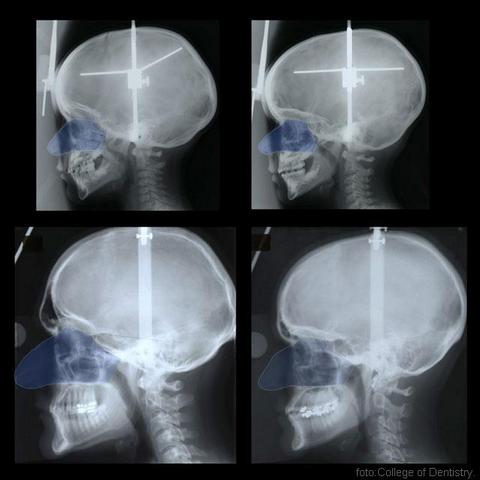

Holton i njegov tim su pratili veličinu i rast nosa 38 pojedinaca evropskog porekla uključenih u projekt „Proučavanje rasta ličnih kostiju i lica“ u dobi od 3 godine pa do srednjih dvadesetih godina žvota. Merenja su se provodila na vanjskom delu nosa i unutrašnjosti nosa u redovnim razmacima i na svakom pojedincu.

Naučnici su otkrili da devojčice i dečaci generalno imaju istu veličinu nosa, od rođenja do počenog stadijuma puberteta (oko 11. godine). Od tog se vremena počinje nazirati razlika, pokazuju merenja.“Čak iako su im tela iste veličine kao i žensko telo,“ objašnjava Holton, „muškarci opet imaju veće noseve. A tek se u pubertetu počinje pokazivati ta razlika“